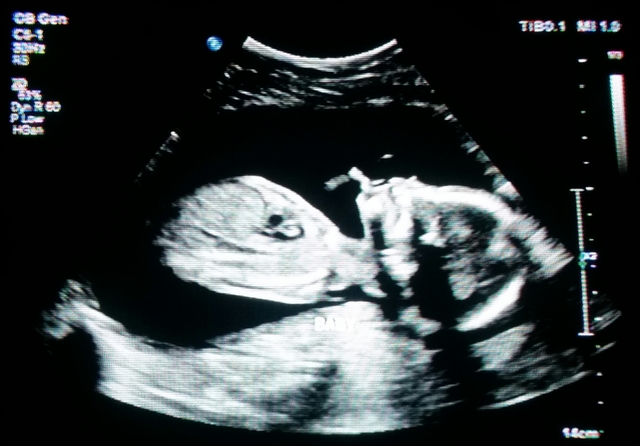

• 1 Month

1 Month

About Mom And Baby During 1 Month: The egg is making its way to the Fallopian tube. The fertilized egg is implanting into the lining of the uterus, you may notice some spotting. This is the month you miss your first period. The baby is developing balls of cells. This is the month to make your first doctors appointment. Facts:

-When pregnant you may be very tired.

-The mood swings can have a big affect on your pregnancy

-The morning sickness may be catching up to you. S/P: The bump.com